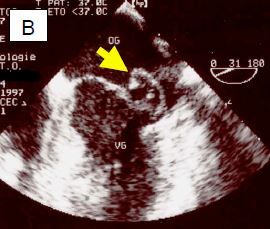

L'échocardiographie démontre que la maladie dégénérative peut prendre plusieurs aspects (Figure 11.64).

Figure 11.64 : Images ETO d’insuffisance mitrale sur dégénérescence myxoïde. A : excès de tissu avec ballonnisation, épaissisement localisé et prolapsus des deux feuillets ; la flèche indique le déplacement de l’extrémité des feuillets en arrière du plan de l’anneau mitral (trait pointillé). B : prolapsus isolé de P2. C : prolapsus de P2 avec rupture de cordage (indiqué par la flèche). D : rupture complète de muscle papillaire avec fragment de pilier attaché à l’extrémité du feuillet antérieur.